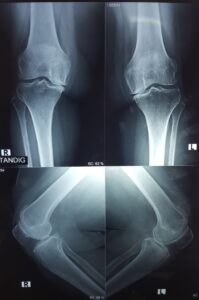

In a normal joint, articular cartilage allows for smooth movement within the joint, whereas in an arthritic knee the cartilage itself becomes thinner or completely absent. In addition, the bones become thicker around the edges of the joint and may form bony “spurs”. All of these factors can cause pain and restricted range of motion in the joint.

- A bow-legged knee deformity

Your doctor will diagnose osteoarthritis based on the medical history, physical examination, and X-rays.

X-rays typically show a narrowing of the joint space in the arthritic knee.